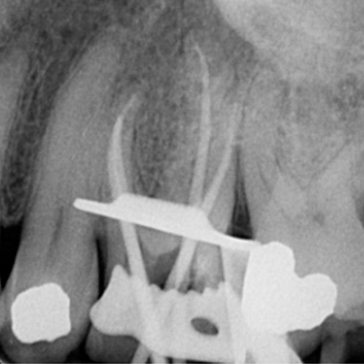

Case 2. RCT of UL6